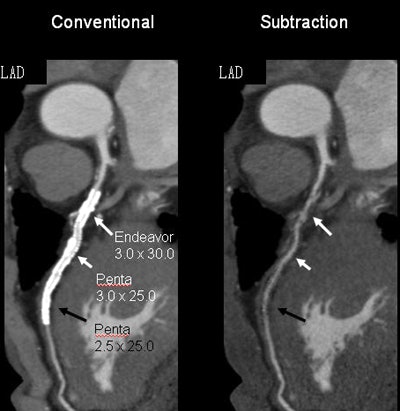

Subtraction coronary CTA did a better job of visualizing the arterial lumen within metallic stents, and it also improved the evaluation of in-stent restenosis, the group reported last month at the RSNA 2014 meeting. More than 80% of stents 2.5 mm in diameter and larger can be evaluated using the technique, which also improved specificity and reduced the number of nonevaluable stents from 56 to four, the researchers found.

Fifty-six stents couldn't be assessed before subtraction, compared with four after subtraction. Among the factors causing stent nonassessability, size was by far the most important, with smaller stents harder to assess.

Still, with the use of DSCTA, stent assessability improved from approximately 78% to 92% for 3.5-mm stents (p = 0.0503), from 61% to 90% for 3.0-mm stents (p = 0.0001), and from 37% to 81% for 2.5-mm stents (p = 0.0001).

"For the larger stents, there was no statistically significant difference" in assessability with or without DSCTA, Amanuma said. However, for 2.5-mm stents, the improvement in assessability was more than 40 percentage points.

"DSCTA improved visualization of the stent lumen, resulting in improved diagnostic capabilities in the evaluation of in-stent restenosis, especially in terms of specificity, which is very important," he said. "The frequency of restenosis is very small, so high specificity is important."

Finally, using DSCTA improves assessability to more than 80% of 2.5-mm stents, an important advance "because 2.5-mm stents are now considered inappropriate for coronary CTA," according to appropriateness criteria, Amanuma said. Careful heart rate control is critical to maintaining these results, he added.